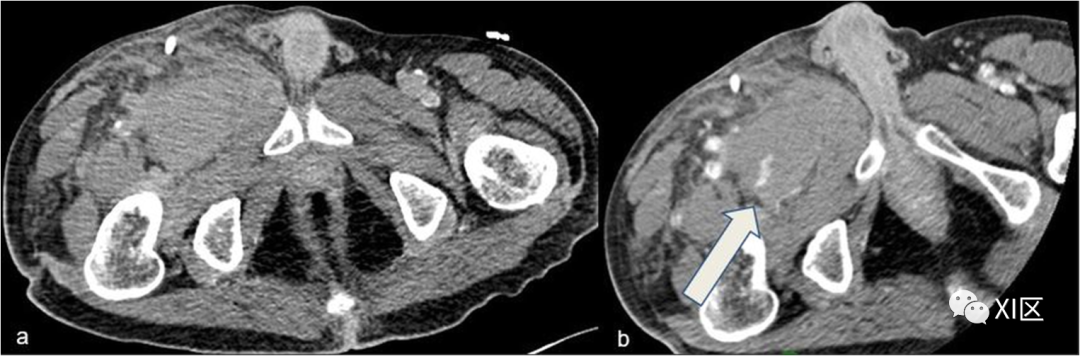

血肿是软组织中的高密度病变;它可能与活动性出血的迹象有关,表现为造影剂外渗(图8)。

图8 腹股沟血肿伴活动性出血。73岁女性,车祸后CTA轴位图像;a 平扫,b 动脉期。在a组,腹股沟处有明显的大血肿;注射造影剂后,出现不规则的血管外增强(箭头)(b),这是持续出血的迹象。右腹股沟前部可见金属碎片

当所有血管壁层都被破坏时,就会发生主动外渗。CTA需要区分持续出血和无活动性出血的血肿。在凝块性血肿中,没有明显的造影剂积聚迹象,而血肿内管腔外造影剂聚集不清或软组织和肌肉浸润则是活动性出血。CTA还可以帮助区分小血管出血(可以保守治疗)和大分支出血(必须手术治疗)。血管横断/闭塞表现为造影剂增强血管腔突然停止/中断,有或无血管远端复发(图9)。